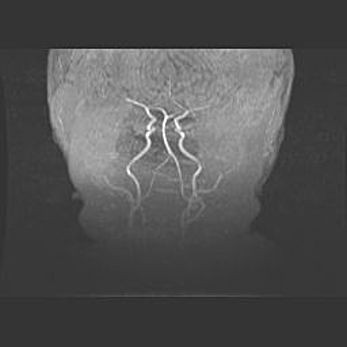

Открытая гидроцефалия.

Возраст: 6 месяцев 15 дней

Вес: 6200 г

Пол: женский

Окружность головы: 41 см

Срок гестации: 38 недель

Гидроцефалия головного мозга у новорожденных – это скопление избыточного количества цереброспинальной жидкости в головном мозге. Ее избыточное скопление в мозге приводит к патологическому расширению желудочков мозга (четырех полостей, расположенных в глубине белого вещества мозга, заполненных цереброспинальной жидкостью и связанных узкими проходами).

Открытый тип гидроцефалии (сообщающаяся) наблюдается тогда, когда нарушен механизм всасывания ликвора в системный кровоток. При этом типе причиной заболевания чаще всего является перенесенные ранее инфекции (например: менингит),  либо же наличие крови в субарахноидальном пространстве.